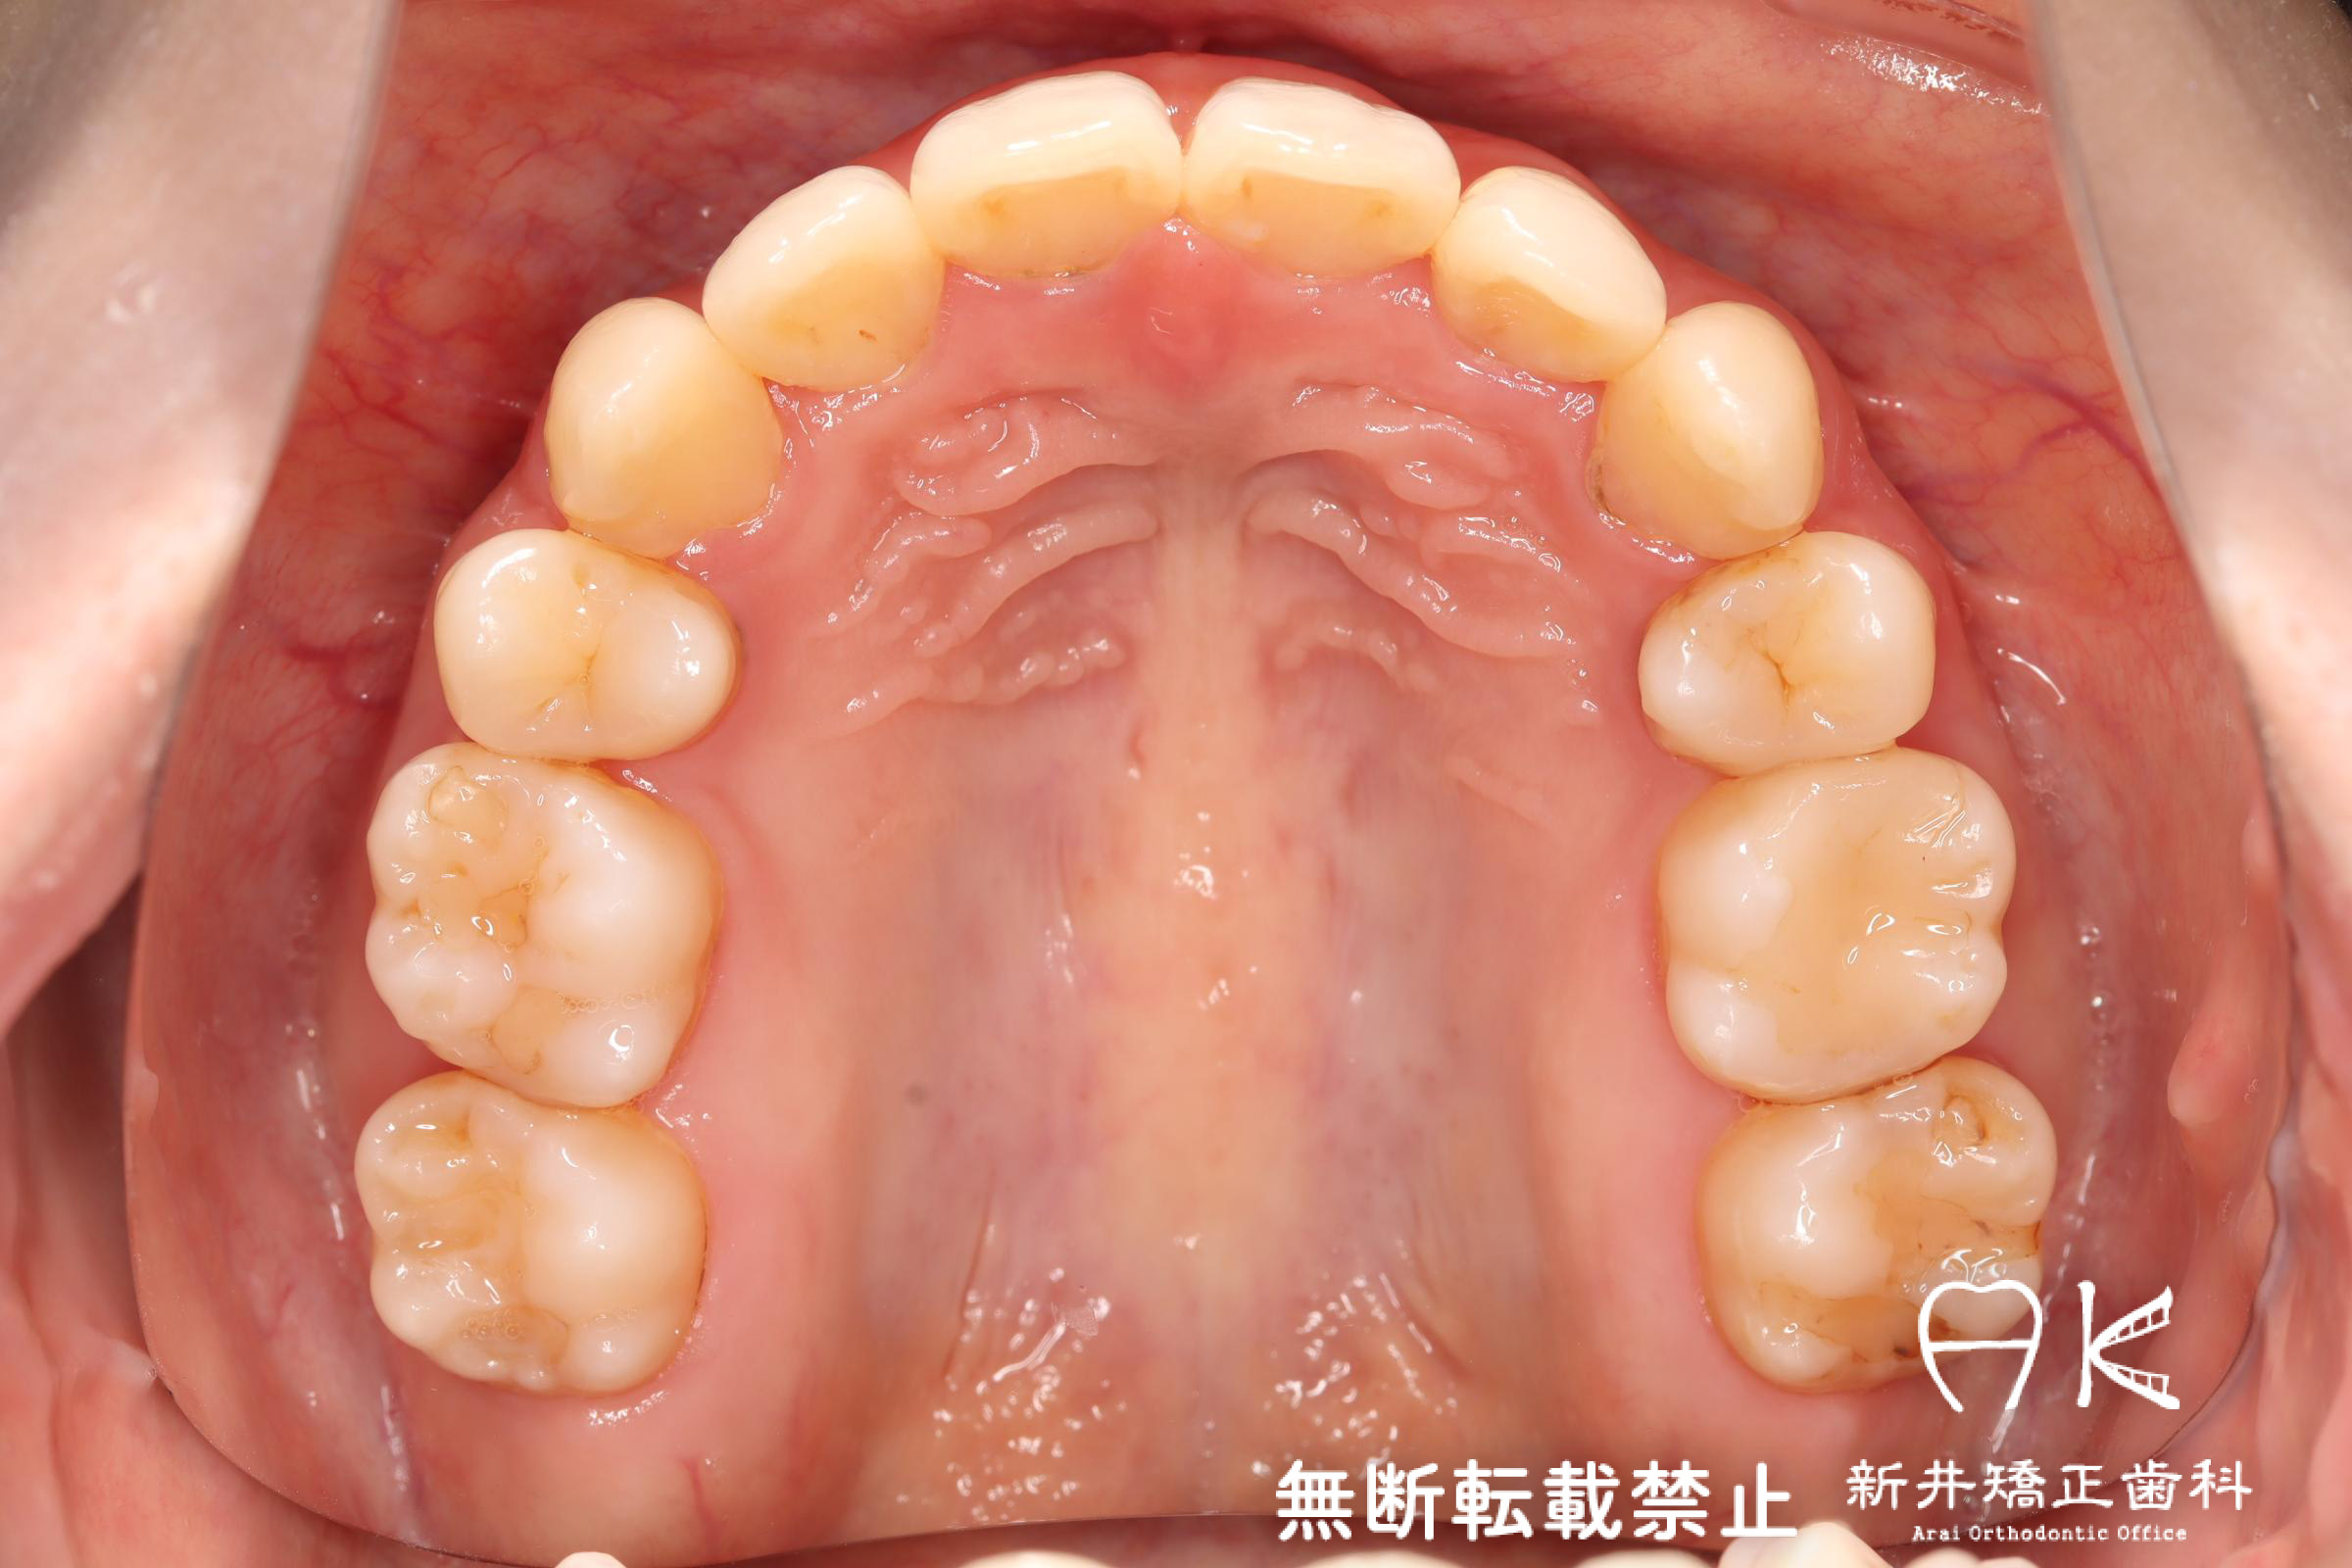

治療前後の解説

| 治療後 | 前歯から奥歯まで全体的に緊密な咬み合わせになっています。 治療前後のセファログラムのトレースの重ね合わせを比較すると、上下の歯列の後方移動ができ、それにより口元もよりすっきりしました。 また前歯の唇側傾斜も改善されています。 |